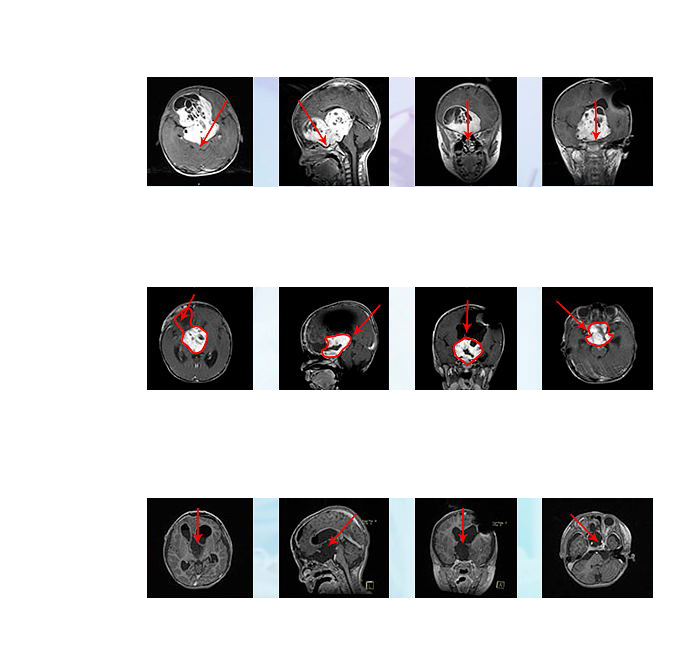

術(shù)后1年,小冬一家來(lái)到INC面對(duì)面咨詢“巴教授”,原本已經(jīng)失明的小冬現(xiàn)在視力漸漸恢復(fù)了,復(fù)查后MRI影像也顯示腫瘤并無(wú)增長(zhǎng),小朋友恢復(fù)了以往的活潑可愛(ài)。

è§??¥????è??è′¨??¤??????

2019年4月,小冬父母帶他來(lái)到INC后面對(duì)面咨詢復(fù)診